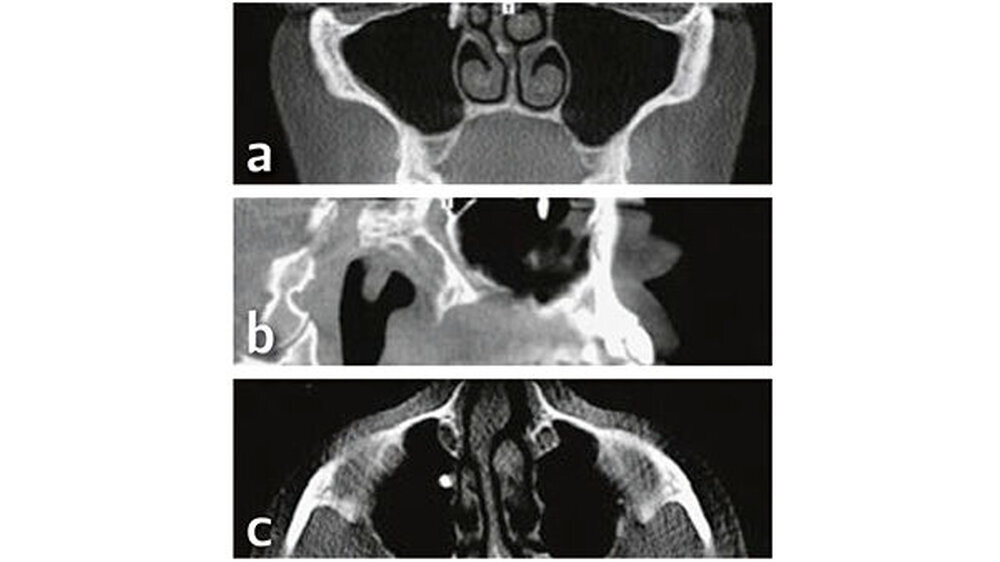

Röntgenologisch (Abb. 1) zeigen sich auf der OPT-Ansicht ein dental und ossär unauffälliger Befund und eine gut belüftete, nicht verschattete rechte Kieferhöhle. Der Verdacht eines Wurzelrests in regio 17 bestätigt sich in dieser Darstellung nicht. Erst nach genauerer Betrachtung der axialen,coronalen und sagittalen Bildebenen des DVT konnte eine zahndichte Verschattung regio Ostium naturale des Sinus maxillaris dargestellt werden, welches kaudal in das Infundibulum ethmoidale und kranial in den Hiatussemilunaris mündet (Abb. 2).